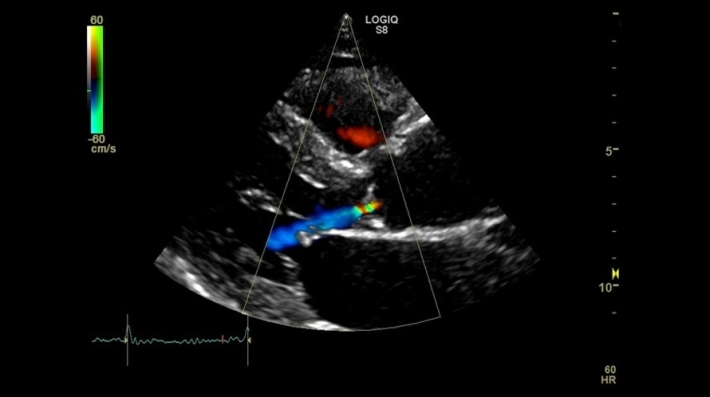

Logiq S8 подходит для диагностики широкого спектра заболеваний и проведения исследований различных анатомических областей, включая брюшную полость, сердечно-сосудистую и скелетно-мышечную системы, молочные железы и другие органы.

• Специализированный сосудистый пакет для высокоточной диагностики сердечно-сосудистой системы.

• CW Doppler Option — опция постоянно-волнового допплера для секторных и карандашных датчиков;

• Tissue Velocity Imaging Option (TVI) — тканевой допплер;

• Stress Echo Option — опция Стресс-эхо;

• Auto EF — опция автоматического недопплеровского измерения глобальной сократительной способности левого желудочка;

• AFI Cardiac Strain — режим автоматической оценки региональной сократительной функции левого желудочка;